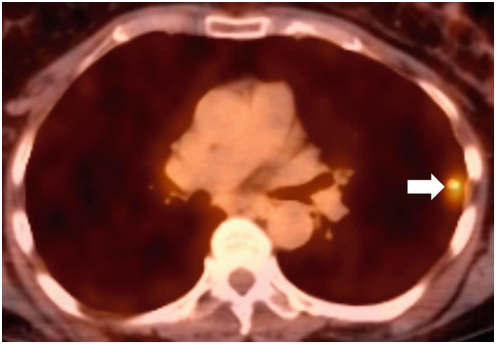

63岁女性患者,吸烟,有15包/年的吸烟史,在另一家医院接受肺部LDCT检查以评估和处理一个肺部结节。LDCT胸部显示左上叶11 mm结节,边缘有毛刺。其他影像学特征包括上叶为主的小叶中心气肿,一些微小的钙化结节,可能是陈旧性肉芽肿,以及两个小的薄壁囊肿(图1)。患者按照建议完成了全身PET/CT扫描。PET/CT扫描显示结节具有(18)F-氟脱氧葡萄糖(FDG)的亲和力,标准摄取值(SUV)为4.2(图2),身体其他部位无异常摄取。患者的症状包括偶尔咳嗽,否认有明显的呼吸急促、发烧、发冷、盗汗、体重减轻及咯血等症状。

图2. 轴向,PET–CT图像显示左上叶结节FDG摄取增加,SUV为4.2(箭头)